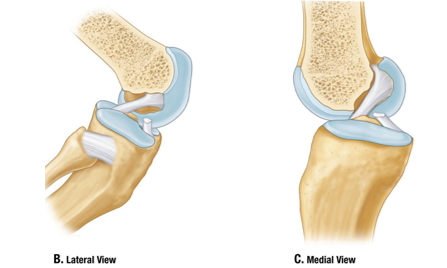

• Menisci

Wedges of fibrocartilage

Deepen articular surface

Shock absorption

Medial Meniscus

•C-shaped

•Broad posteriorly

•Firmly attached to TCL

Lateral Meniscus

•Circular

•Freely moveable

•Attachment for popliteus